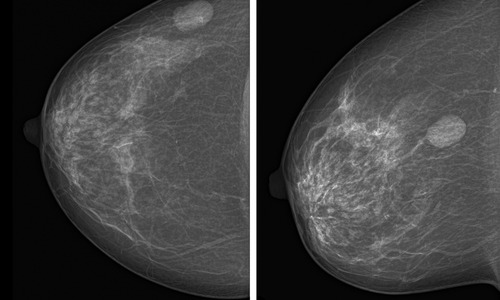

Różnego rodzaju guzki to najczęściej występujące zmiany w piersiach kobiet. Mogą pojawić się w różnym wieku i mają różne podłoże. Najczęściej są nieszkodliwe i nie mają podłoża nowotworowego. W każdym wypadku pojawienie się guzka powinno być skonsultowane z lekarzem w celu dokonania diagnozy.

Zachowanie zdrowych piersi to istotny element profilaktyki raka piersi, który jest jednym z najczęściej diagnozowanych nowotworów u kobiet. Zrozumienie podstawowych informacji dotyczących zmian nowotworowych w piersiach, czynników ryzyka oraz metod profilaktyki i wczesnego wykrywania jest kluczowe.